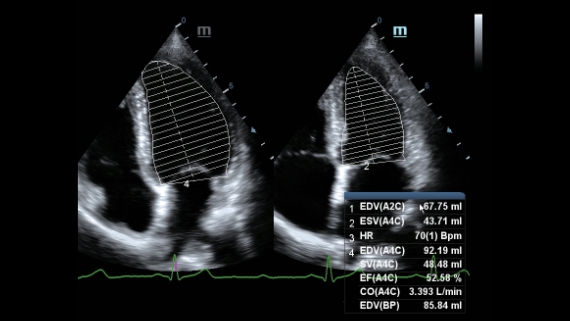

Dedicated Care for ECHO

As an all-around partner, DC-60 ECHO with X-Insight devotes to provide a comprehensive solution to help you manage all-aspect daily clinical practice with ease and certainty.

Based on the deep insights of customer needs, the DC-60 ECHO with X-Insight is designed to deliver high efficiency with precision imaging, which is empowered by eXpress Clarity, eXceptional Intelligence and eXceeding Experience.